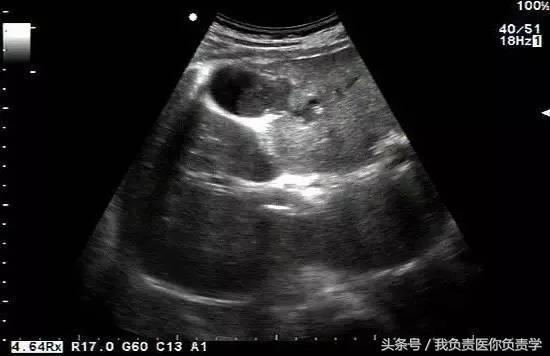

典型病例 1

患者男,64岁,因右上腹疼痛半月余就诊。查体发现右上腹部轻压痛,无发热。超声检查所见如下:

图1示胆囊增大,囊壁增厚,囊内透声差

图3示胆囊与囊性回声区间隐约可见裂隙相通

图4和5为局部放大图像,可见胆囊与囊性回声区间可见直径约2mm的通道

超声检查考虑为胆囊炎合并胆囊穿孔,后经CT检查证实。